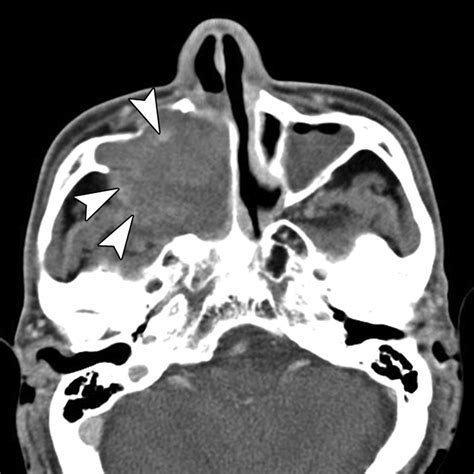

The results of a Mxailliary Sinus CT scan are interpreted by a radiologist, who will look for signs of:

• Inflammation: Swelling or infection in the sinuses.

• Obstruction: Blockages in the sinus passages.

• Abnormal Growths: Polyps, tumors, or other growths.

• Structural Issues: Deviated septum or other structural abnormalities.

Common Findings in a Mxailliary Sinus CT Scan

Some common findings in a Mxailliary Sinus CT scan include:

• Sinusitis: Inflammation of the sinuses, often due to infection.

• Nasal Polyps: Benign growths in the nasal passages.

• Tumors: Abnormal growths that may be benign or malignant.

• Fractures: Bone fractures in the sinus area, often due to trauma.

• Deviated Septum: A misaligned nasal septum that can cause obstruction.